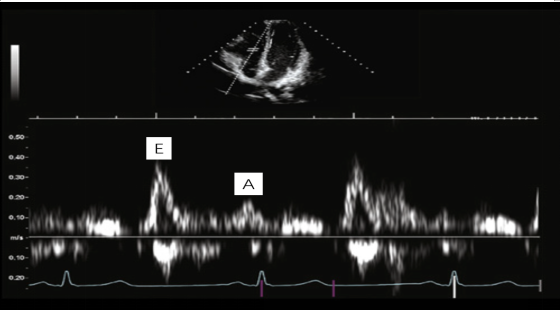

(6)三尖瓣瓣口舒张期血流频谱图19:采用脉冲多普勒模式(PW),取样点在三尖瓣瓣口下1 cm,在心尖四腔心切面上进行测量,获得三尖瓣口舒张早期峰值速度E,三尖瓣口心房收缩期(心室舒张晚期)峰值速度A,E/A,E峰减速时间(EDT)等。参考值为E峰:57±8 cm/s;A峰:39±6cm/s;E/A:>1;EDT:225±28 ms。

图片

19. 三尖瓣瓣口舒张期血流频谱

一般来说,三尖瓣瓣口舒张期血流频谱E/A<0.8提示为松弛受损;0.8<E/A<2.1,伴E/E′>6提示E/A为假性正常,右心室舒张功能中度受损;E/A>2.1伴EDT<120 ms,右心室充盈受限。结合前面的三尖瓣瓣环侧壁组织多普勒(TDI),Em/Am<1为右心室舒张功能受损;E/Em>6提示右心房压升高。根据三尖瓣瓣口血流频谱图,我们也可以获得有无前向血流加速的相关信息。